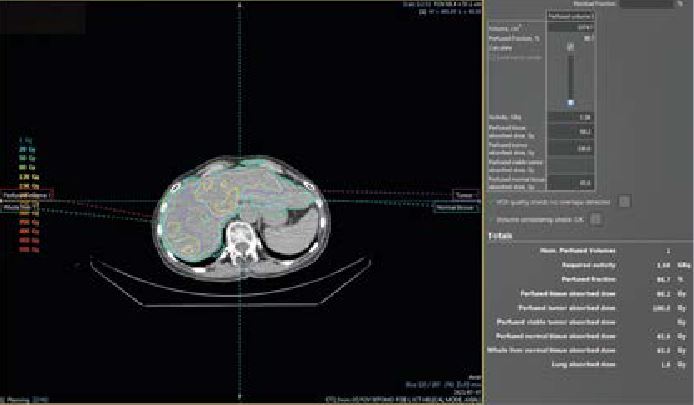

• Par Yttrium 90 afin de réaliser une radioembolisation hépatique (cancer primitif ou métastase)